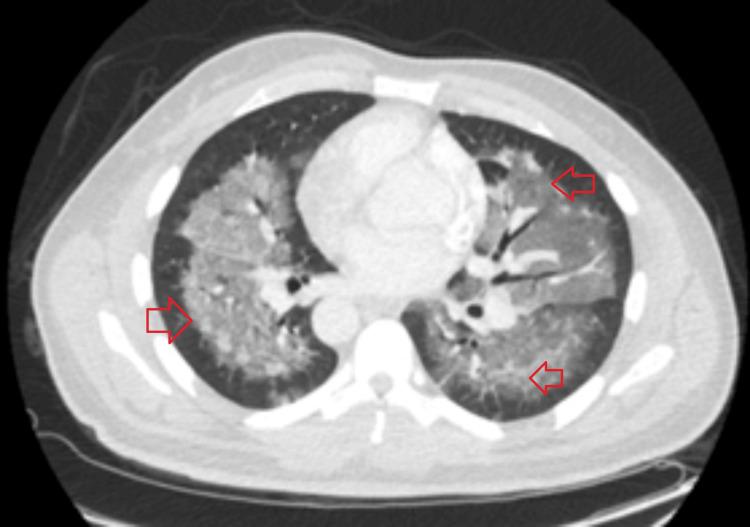

Pulmonary infiltrates, arising from diverse etiologies such as infections, cardiac conditions, or parenchymal diseases, present a diagnostic challenge. Drug-induced pneumonitis, although less common, should be considered, especially when symptoms develop after medication initiation. This case report highlights a rare yet significant complication of antibiotic therapy, daptomycin-induced eosinophilic pneumonia (DIEP). A 56-year-old male with a history of type 2 diabetes mellitus, hypertension, and renal insufficiency presented with pleuritic chest pain and a productive cough for two days. Chest X-ray and CT imaging revealed bilateral scattered airspace opacities and ground-glass opacities, suggesting pneumonia or pulmonary edema. Initially treated for healthcare-associated pneumonia, the patient's condition persisted despite therapy. His medical history included osteomyelitis treated with vancomycin, later switched to daptomycin. Two weeks after the switch, the patient developed new respiratory symptoms. A bronchoalveolar lavage (BAL) was performed to establish the diagnosis of eosinophilic pneumonia. BAL showed >25% eosinophils, confirming daptomycin-induced eosinophilic pneumonia. The antibiotic was discontinued, and prednisone 40 mg daily was initiated, leading to the resolution of symptoms. Daptomycin, an antibiotic commonly used to treat gram-positive infections, can rarely cause eosinophilic pneumonia, a rare adverse reaction characterized by pleuritic chest pain, dyspnea, and diffuse ground-glass opacities on imaging. The mechanism remains unclear but may involve surfactant binding, leading to alveolar epithelial injury. Diagnosis is confirmed through BAL, with eosinophilia greater than 25%. Management consists of discontinuing daptomycin and initiating steroids if necessary. This case underscores the importance of early recognition and prompt discontinuation of the offending drug, along with the use of steroids in cases with severe symptoms. BAL is a key diagnostic tool in confirming drug-induced eosinophilic pneumonia. In conclusion, daptomycin-induced eosinophilic pneumonia is a rare but significant complication requiring vigilance in patients treated with the drug. Early diagnosis and effective management are crucial for achieving favorable outcomes.

肺部浸润由多种病因引起,如感染、心脏疾病或实质性疾病,这给诊断带来了挑战。药物性肺炎虽不太常见,但也应予以考虑,尤其是在用药后出现症状的情况下。本病例报告强调了抗生素治疗一种罕见但严重的并发症,即达托霉素诱导的嗜酸性粒细胞性肺炎(DIEP)。一名56岁男性,有2型糖尿病、高血压和肾功能不全病史,出现胸膜炎性胸痛和咳痰2天。胸部X线和CT成像显示双侧散在的气腔实变和磨玻璃影,提示肺炎或肺水肿。最初按医疗保健相关肺炎进行治疗,尽管进行了治疗,患者病情仍持续。他的病史包括用万古霉素治疗的骨髓炎,后来改用达托霉素。换药两周后,患者出现了新的呼吸道症状。进行了支气管肺泡灌洗(BAL)以确诊嗜酸性粒细胞性肺炎。BAL显示嗜酸性粒细胞>25%,证实为达托霉素诱导的嗜酸性粒细胞性肺炎。停用抗生素,并开始每日服用40mg泼尼松,症状得以缓解。达托霉素是一种常用于治疗革兰氏阳性感染的抗生素,很少会引起嗜酸性粒细胞性肺炎,这是一种罕见的不良反应,其特征为胸膜炎性胸痛、呼吸困难以及影像学上的弥漫性磨玻璃影。其机制尚不清楚,但可能涉及表面活性剂结合,导致肺泡上皮损伤。通过BAL确诊,嗜酸性粒细胞增多大于25%。处理措施包括停用达托霉素,必要时开始使用类固醇。本病例强调了早期识别和及时停用致病药物的重要性,以及在症状严重的病例中使用类固醇的重要性。BAL是确诊药物性嗜酸性粒细胞性肺炎的关键诊断工具。总之,达托霉素诱导的嗜酸性粒细胞性肺炎是一种罕见但严重的并发症,在用该药物治疗的患者中需要保持警惕。早期诊断和有效管理对于取得良好预后至关重要。